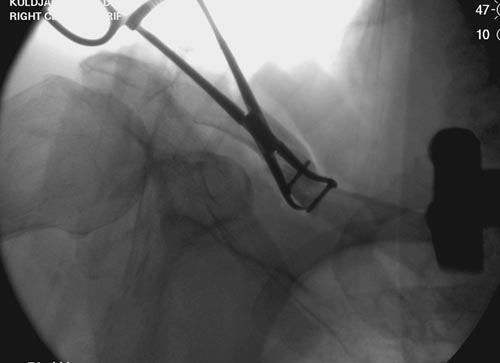

Болезненные ложные суставы надо оперировать, и здесь представлен случай

свежего болезненного ложного сустава, оперированного через 4 месяца.

Освобожден средний фрагмент и боковая компрессия лагированием, фиксация

пластиной..